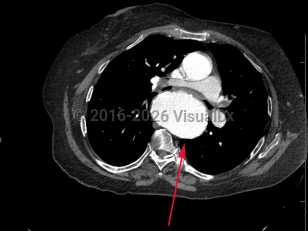

TAA is the dilatation of the artery compared to its original size; it is usually defined as the typical diameter of the artery increasing by 50%. A TAA will rarely manifest with symptoms, and about 95% of patients are asymptomatic. Catastrophic complications of TAA include aortic dissection and rupture, which are medical emergencies with high mortality rates. Most of these complications occur in the root or ascending aorta, followed by the descending aorta and aortic arch, respectively.

Biochemical and mechanical forces lead to TAA causing wall weakness and expansion. Changes in aortic wall compliance lead to increased stress on the artery and during systolic impulse can further exacerbate wall fragility, leading to aneurysms. Several factors that can lead to rupture or dissection include but are not limited to aortic ulcers (disrupted atherosclerotic plaques), intimal atherosclerosis, and intramural hematomas. Infectious aortitis can cause pseudoaneurysms (false aneurysms that occur at the site of arterial injury from infection or trauma).

Management depends on the location, shape, and size of the aneurysm, as well as symptoms and concomitant cardiovascular disease. In asymptomatic patients, management may consist of blood pressure control, specifically with beta blockers for impulse control, surveillance, and patient education to watch for early signs and symptoms of complications. Following complete evaluation and risk assessment, surgical repair or replacement may be undertaken. Less than half of patients who have a ruptured TAA survive to the hospital. Mortality can be as high as 54% within 6 hours and 76% at 24 hours of rupture.